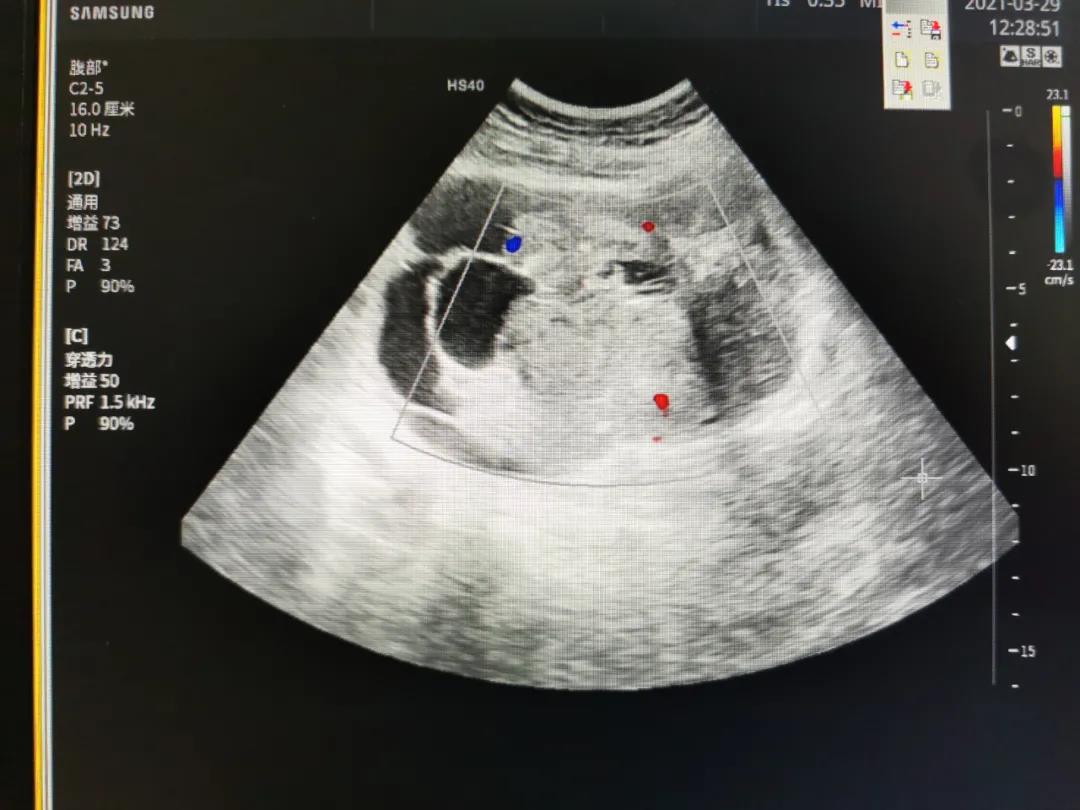

检查发现,唐阿姨盆腔有约14cm大小包块(囊实性混合,以实性为主),子宫实质回声改变。肿瘤标志物CA125、HE4检测明显升高。

(唐阿姨B超检查影像)

结合检查报告及多年的从医经验,业务副院长冷艳主任医师立即察觉到这是一个不好的情况,卵巢有恶性肿瘤的可能性偏大,建议尽快手术治疗,唐阿姨及家属同意。